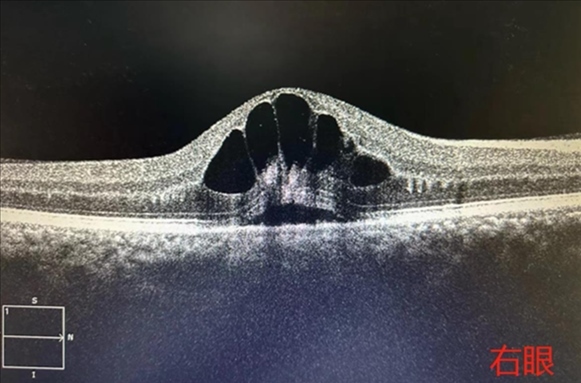

·男子胡吃海喝一周后眼底“長(zhǎng)出花瓣”,眼科專家提醒:假期應(yīng)健康飲食。